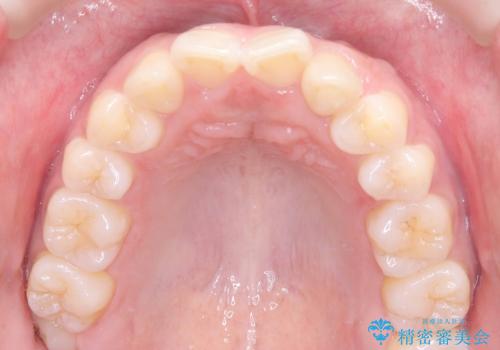

- 「歯の捻じれとがたつき」を主訴に来院された患者様です。

軽度な捻転と叢生だったため、インビザラインのモデレートで治療を行いわずか半年で治療を終える事が出来ました!

目立たないマウスピース矯正【インビザライン】を使用し、

わずか6ヵ月で歯並びがキレイに整いました!